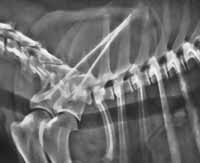

El diagnóstico debe realizarlo siempre un veterinario. Normalmente es preciso llevar a cabo una exploración física completa (para descartar que nuestro perro tenga, además, otras enfermedades), y suele ser necesario un estudio radiológico del cuello y del tórax. En ocasiones, el veterinario realizará un estudio fluoroscópico para observar los movimientos de la tráquea durante la inspiración y espiración. Éste es el método ideal para el diagnóstico puesto que el colapso traqueal no es constante, sino que varía en función de la fase respiratoria. Otras veces el veterinario puede optar por llevar a cabo un estudio endoscópico de la tráquea para visualizar in situ el estado de la membrana dorsal de la tráquea y el grado de alteración traqueal que existe (fotografía 6; Radiografía de tórax donde se aprecia una tráquea normal) (fotografía 7; Radiografía de tórax donde se aprecia un colapso traqueal).